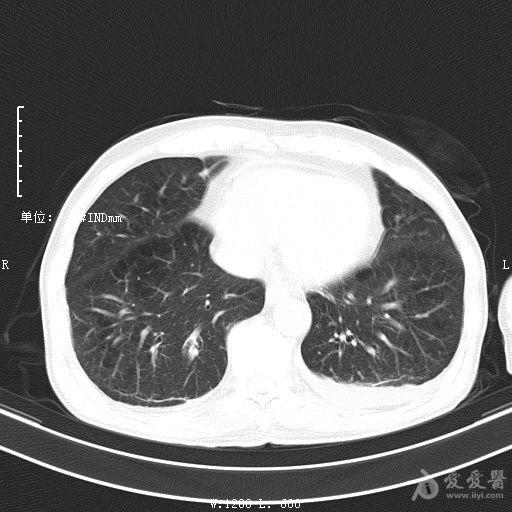

最新的肺炎疫情形勢(shì)嚴(yán)峻,病毒變異使得防控工作更加復(fù)雜,許多地方出現(xiàn)了新的病例,甚至有些地區(qū)的疫情出現(xiàn)了反彈,這不僅是對(duì)醫(yī)療系統(tǒng)的考驗(yàn),更是對(duì)每一個(gè)生命的考驗(yàn),我們需要密切關(guān)注疫情動(dòng)態(tài),共同應(yīng)對(duì)這場(chǎng)挑戰(zhàn)。??